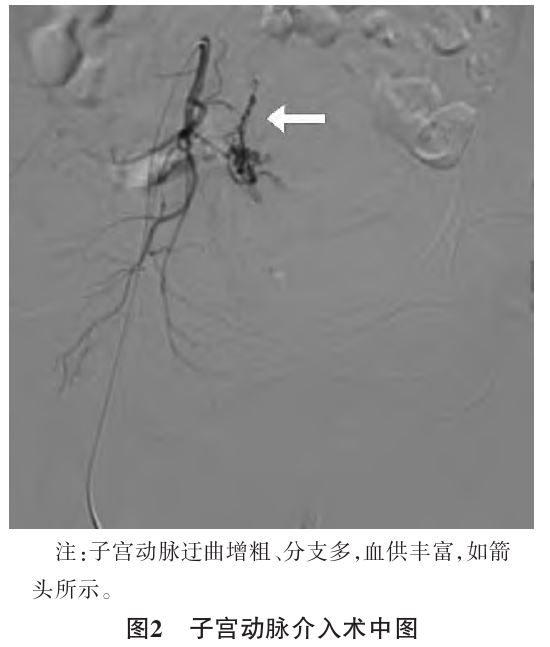

5.67μg/mL。15:40查体:呼吸20次/min,心率74次/min,血压105/56 mmHg,脉搏血氧饱和度0.94,贫血貌,乏力,嗜睡。生命体征逐渐恢复平稳,15:50到达介入室,行双侧子宫动脉栓塞术(见图2),手术过程顺利,术后拔出宫腔球囊引流管

2.3本例宫腔镜下诊断性刮宫术中急性失血性休克原因分析①解剖学异常:盆腔CT示子宫及双侧附件较多明显增粗迂曲杂乱血管影,双侧卵巢静脉增粗,右侧明显且右侧髂内静脉明显增粗迂曲。子宫动脉造影+双侧子宫动脉栓塞术中见子宫动脉迂曲增粗、分支多,血供丰富。在术中因手术操作导致血管损伤进一步导致大出血,且术前由于宫腔内占位性病变性质尚不明确,未在术前使用雌激素提高子宫肌层对宫缩剂的敏感性。②患者术前复查凝血相关项目无明显异常,但系房间隔缺损封堵术后,于心内科规律复查凝血功能调整抗凝药,该病史可能隐藏稽留流产相关的凝血功能障碍。③患者停经时间较长,胎儿及胎盘机化组织、残留组织与子宫壁肌层粘连或向肌层深层嵌入,组织与子宫肌层分界不清,组织粘连易损伤肌层及周围血管导致大出血。④诊断性刮宫术中退变的胎盘组织被破坏后大量释放凝血活酶进入母血循环,引起凝血功能障碍,造成术中出血增加。⑤胚胎死亡后,胎儿血管内皮细胞及上皮细胞损伤,释放大量的组织因子进入母体循环系统,引起凝血功能障碍[4]。⑥患者系多发性子宫肌瘤,肌瘤周围血管较丰富,可能导致子宫肌层侧支循环丰富,且肌瘤也可导致宫腔变形,导致宫腔镜手术操作困难及出血风险较大。该患者发生急性失血性休克时及时纠正休克、积极扩容、输血纠正贫血、宫腔球囊压迫止血、急诊行双侧子宫动脉栓塞治疗,挽救了患者生命,且为二次手术提供了较好的手术时机和条件,避免了切除子宫。